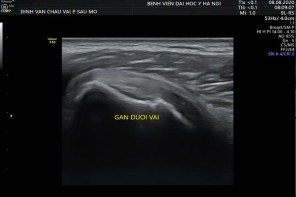

+ Siêu âm gân cơ dưới vai:

Tư thế: tay xoay ngoài, khuỷu gấp 900, lòng bàn tay ngửa

Kỹ thuật: thực hiện các lát cắt ngang và dọc theo gân, có thể thay đổi tư thế xoay trong và xoay ngoài trong khi thực hiện.

Hình 2.30. Hình ảnh siêu âm khảo sát cơ dưới vai

* Nguồn: ảnh chụp trong mổ của BN Trần Huy T, số bệnh án 1909030544